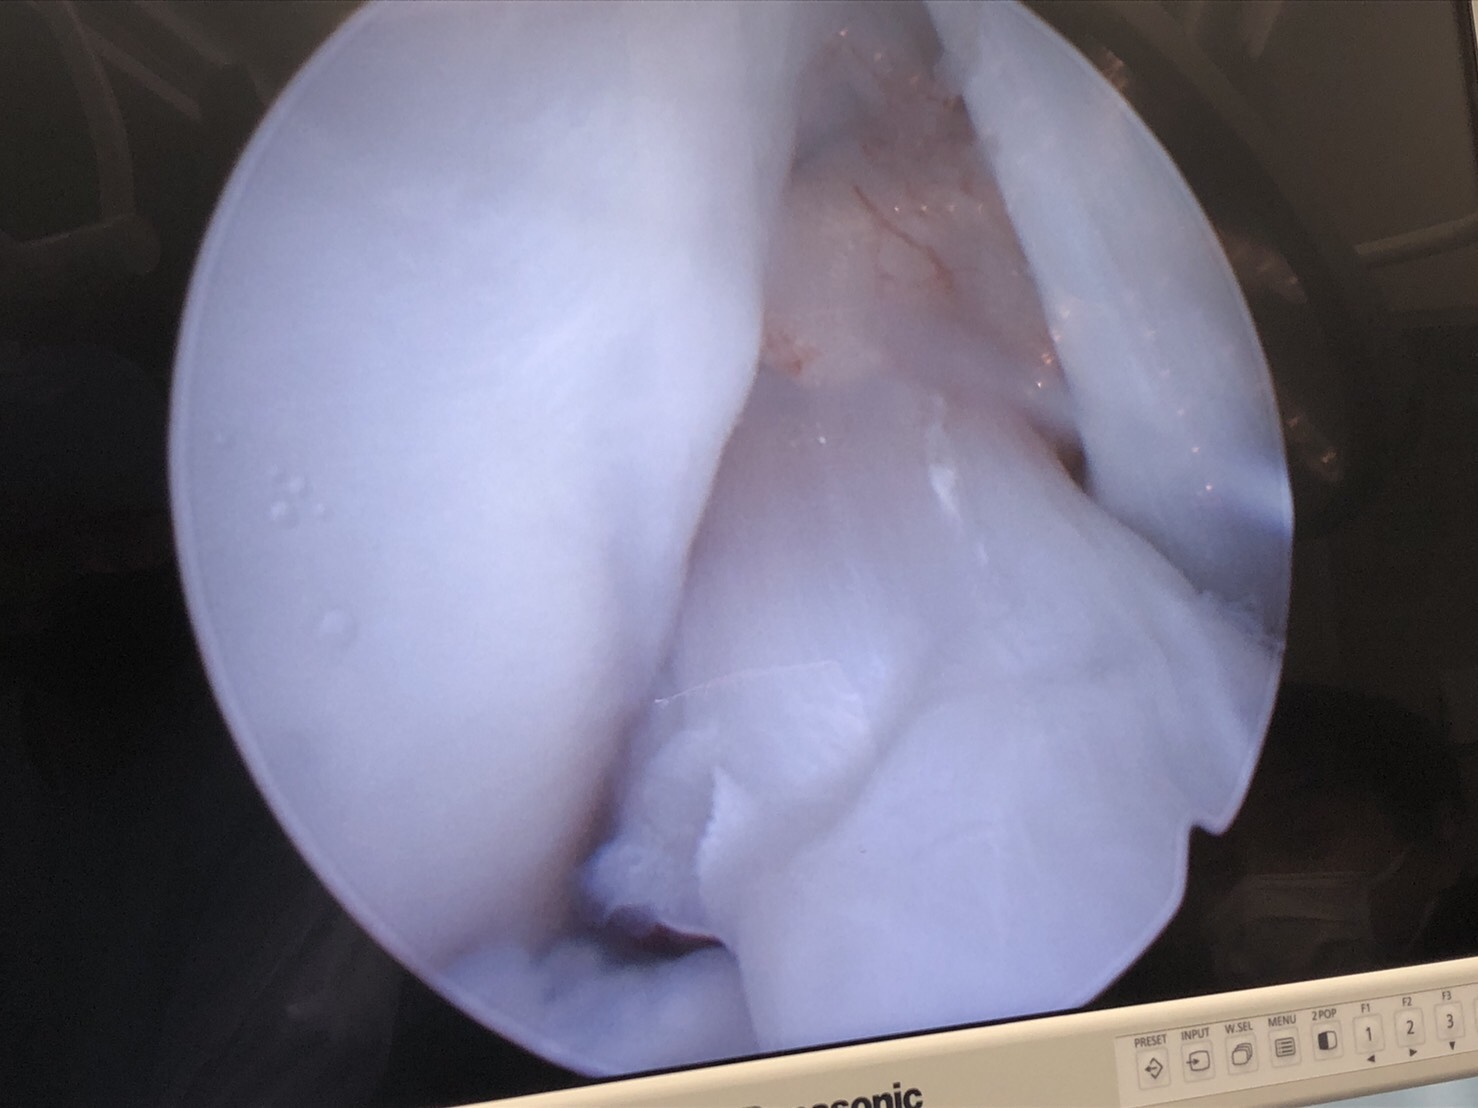

関節鏡検査では前十字靭帯断裂、半月板をメインに観察しており、一部血管が入り込んでいる場所があったものの断裂所見や損傷所見は認められませんでした。